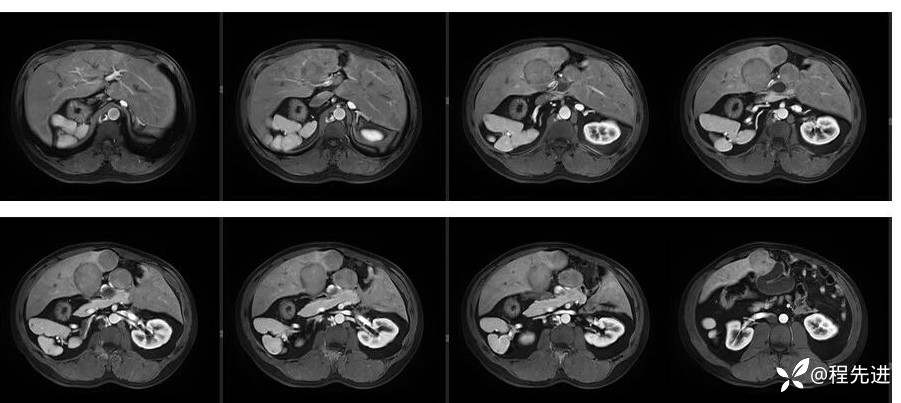

辅助检查:上腹部平扫+增强扫描提示:肝脏、脾脏、胰腺 、胃十二指肠左右倒置,脾脏形态失常,呈分叶团块状,考虑发育变异。肝左右交界区多发肿块,考虑:上皮样血管内皮瘤可能性大,或转移瘤?其它?请结合临床。脂肪肝。肝门胆管局限性扩张。胆囊折叠,壁稍增厚,慢性炎症?胰腺下方椭圆形结节,副脾?

影像检查